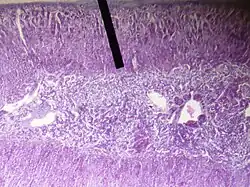

Caracterização histológica

Histologicamente, a zona reticular é formada por células menores e mais compactas do que as das zonas adjacentes. Estas células contêm núcleos esféricos, citoplasma eosinofílico e numerosas mitocôndrias de crista tubular. Estão dispostas em cordões irregulares anastomosados, entrelaçados por sinusoides capilares fenestrados. Há abundância de lipofuscina, que confere coloração mais escura à zona reticular quando comparada às demais regiões do córtex adrenal.[3]